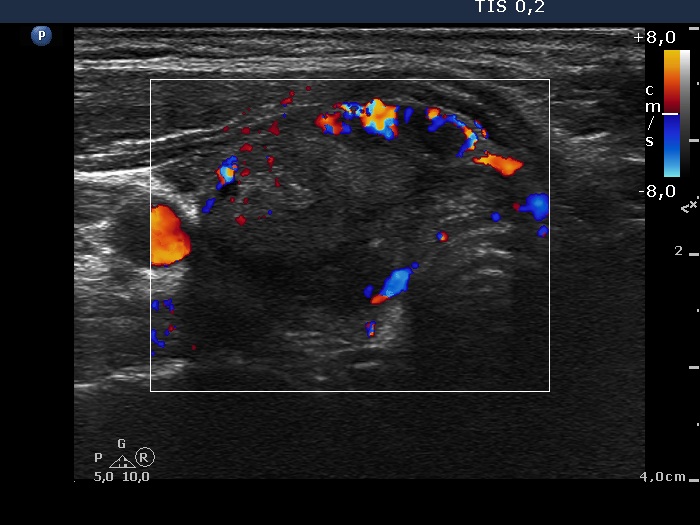

Ultrasonography: the thyroids were echonormal. There was an echonormal nodule occupying almost the entire right lobe. The lesion displayed a halo sign, cystic degeneration and presented perinodular blood flow.

5 sessions of sclerotherapy were performed. We demonstrate the 1st and 4th session.